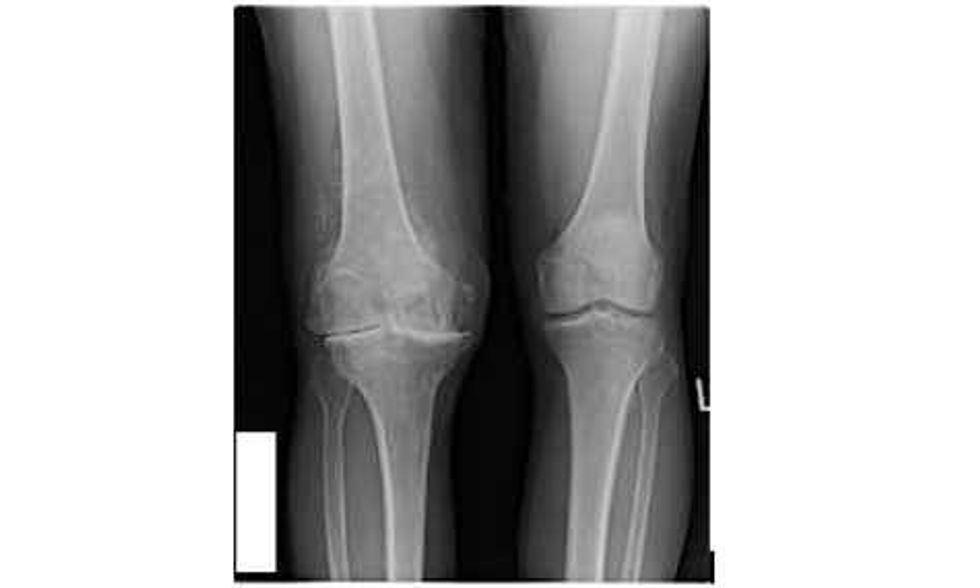

Çfarë nyje është gjuri?

Gjuri është nyje që ka lëvizje vetëm në një drejtim. Përbëhet nga tri kocka, të cilat te gjuri i shëndoshë janë të mbështjella me kërce kockore. Kërci i shëndoshë mundëson lëvizjen e lirë pa dhembje të gjurit.

Artriti i gjurit është shkaktari më i shpeshtë për t’iu nënshtruar këtij operimi. Artriti dëmton kërcin dhe shkakton që sipërfaqet e nyjës të mos jenë të lëmuara. Si pasojë, lëvizja dhe ecja janë të përcjella me dhembje, kurse nyja humb amplitudën e lëvizjeve dhe humbet forca muskulore. Shpeshherë gjuri ënjtet dhe mbushet me sasi të tepërt të lëngut nyjor. Kur i keni këto simptoma, mjeku do t‘ju rekomandojë këtë intervenim. Sot, mosha nuk është faktor limitues për të vendosur protezën e gjurit – mund të kryhet praktikisht në të gjitha moshat. Megjithatë, janë disa faktorë që duhet marrë parasysh, si: sëmundjet tjera, mosha biologjike (vitaliteti i pacientit) etj.

Së pari duhet të informoheni nga mjeku për gjendjen tuaj. Për këtë, ai do të kërkojë incizime radiografike dhe analiza për të arritur deri te diagnoza. Pastaj mjeku do t’ju japë opsionet e trajtimit. Nëse jeni kandidat për një protezë të gjurit, vendimi i parë që duhet ta merrni është koha kur do ti nënshtroheni operimit. Për këtë duhet të merrni parasysh disa faktorë, në rend të parë të informoheni për kohëzgjatjen e procesit. Pra, ky është operim që mund dhe duhet planifikuar.